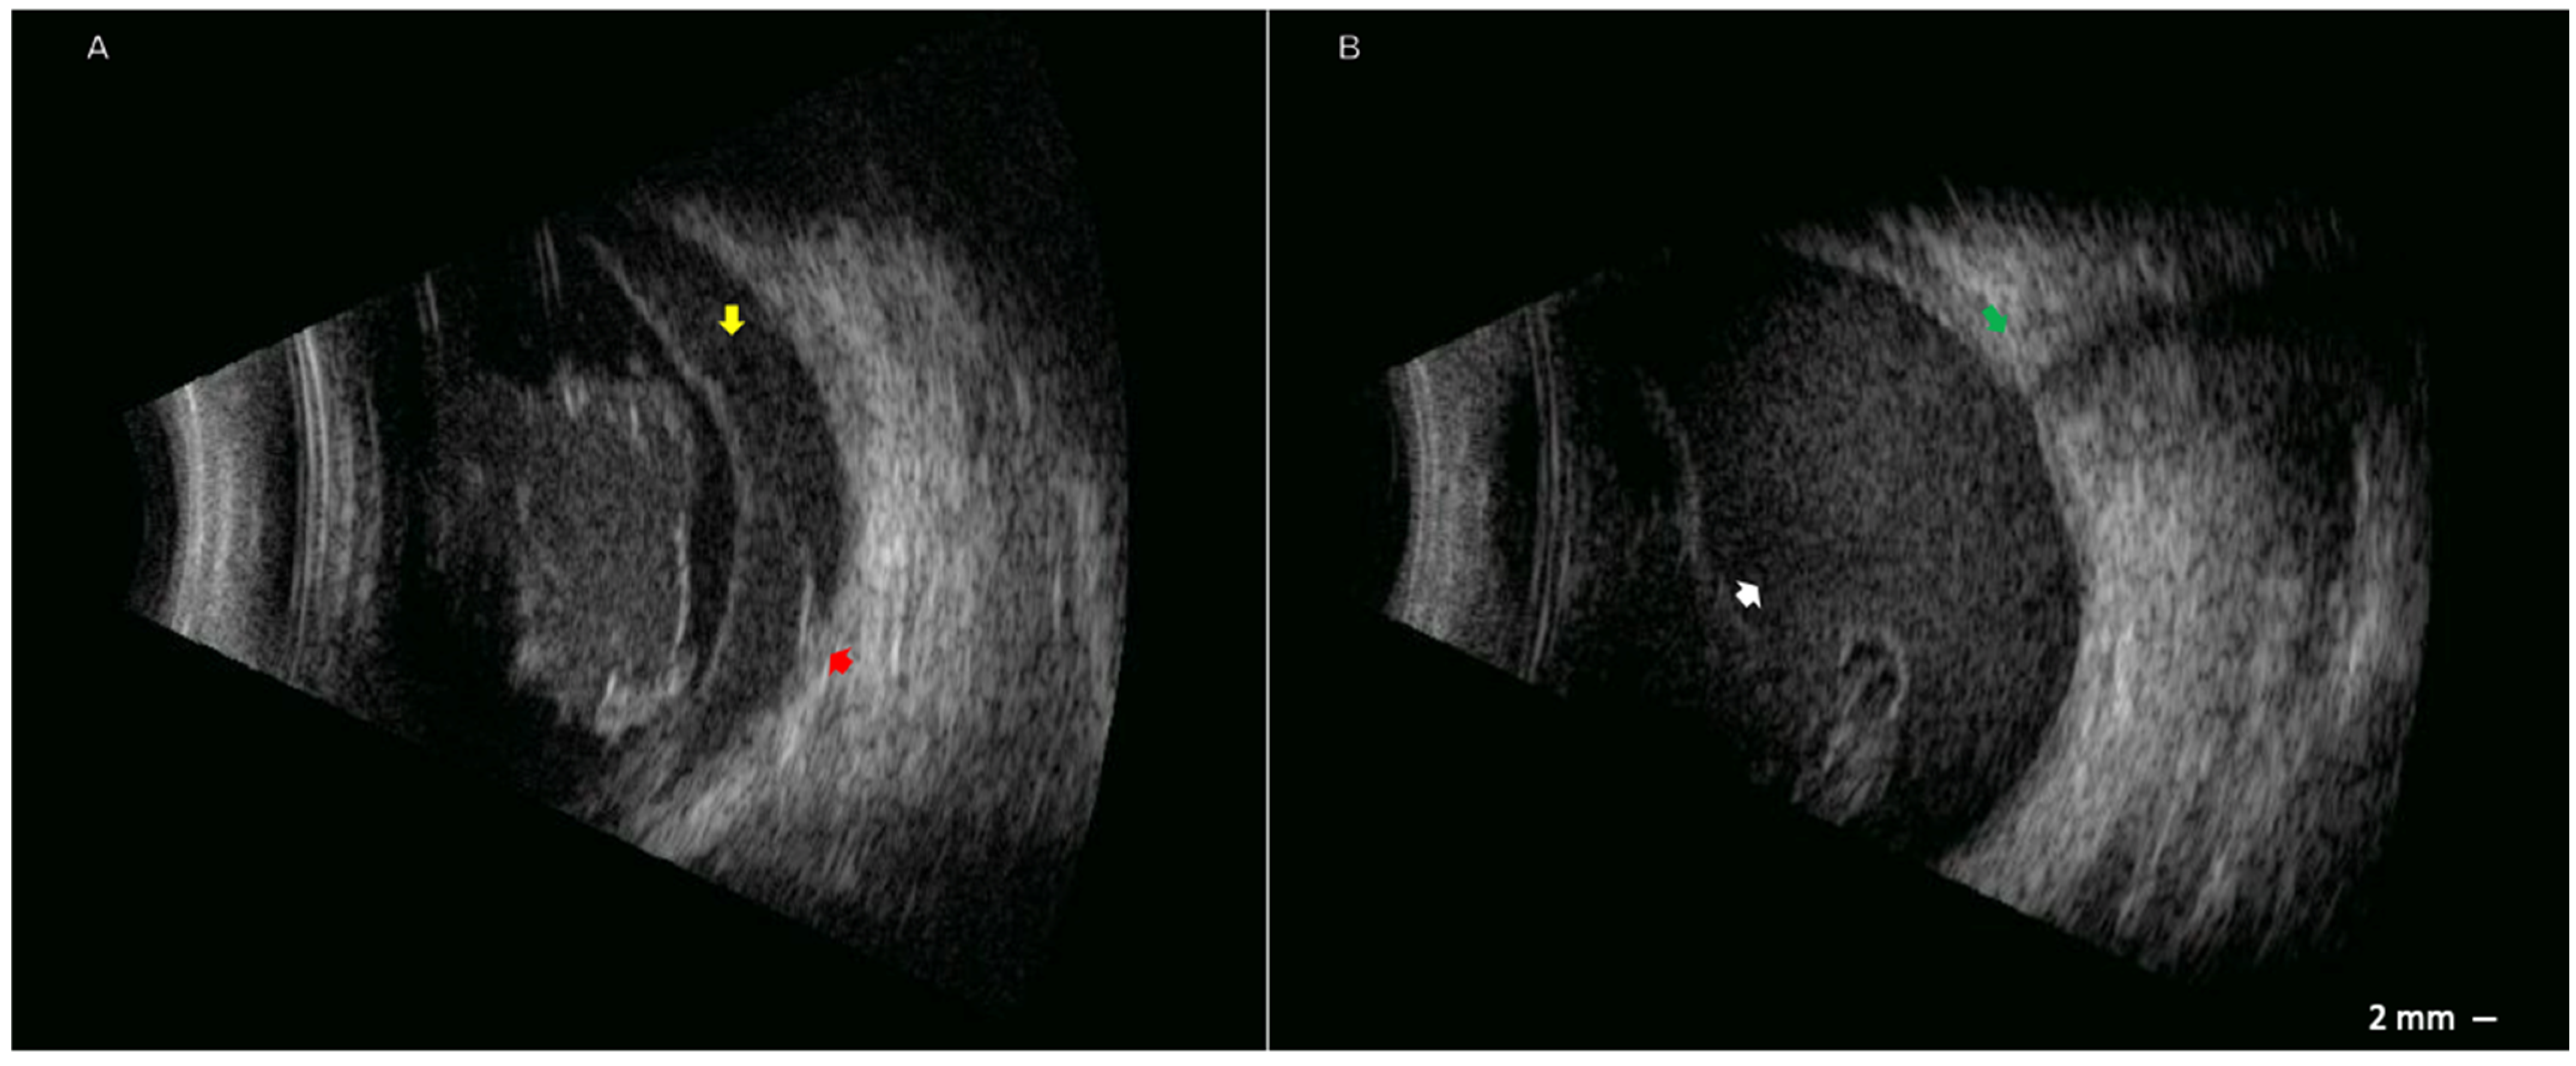

2. Case Presentation